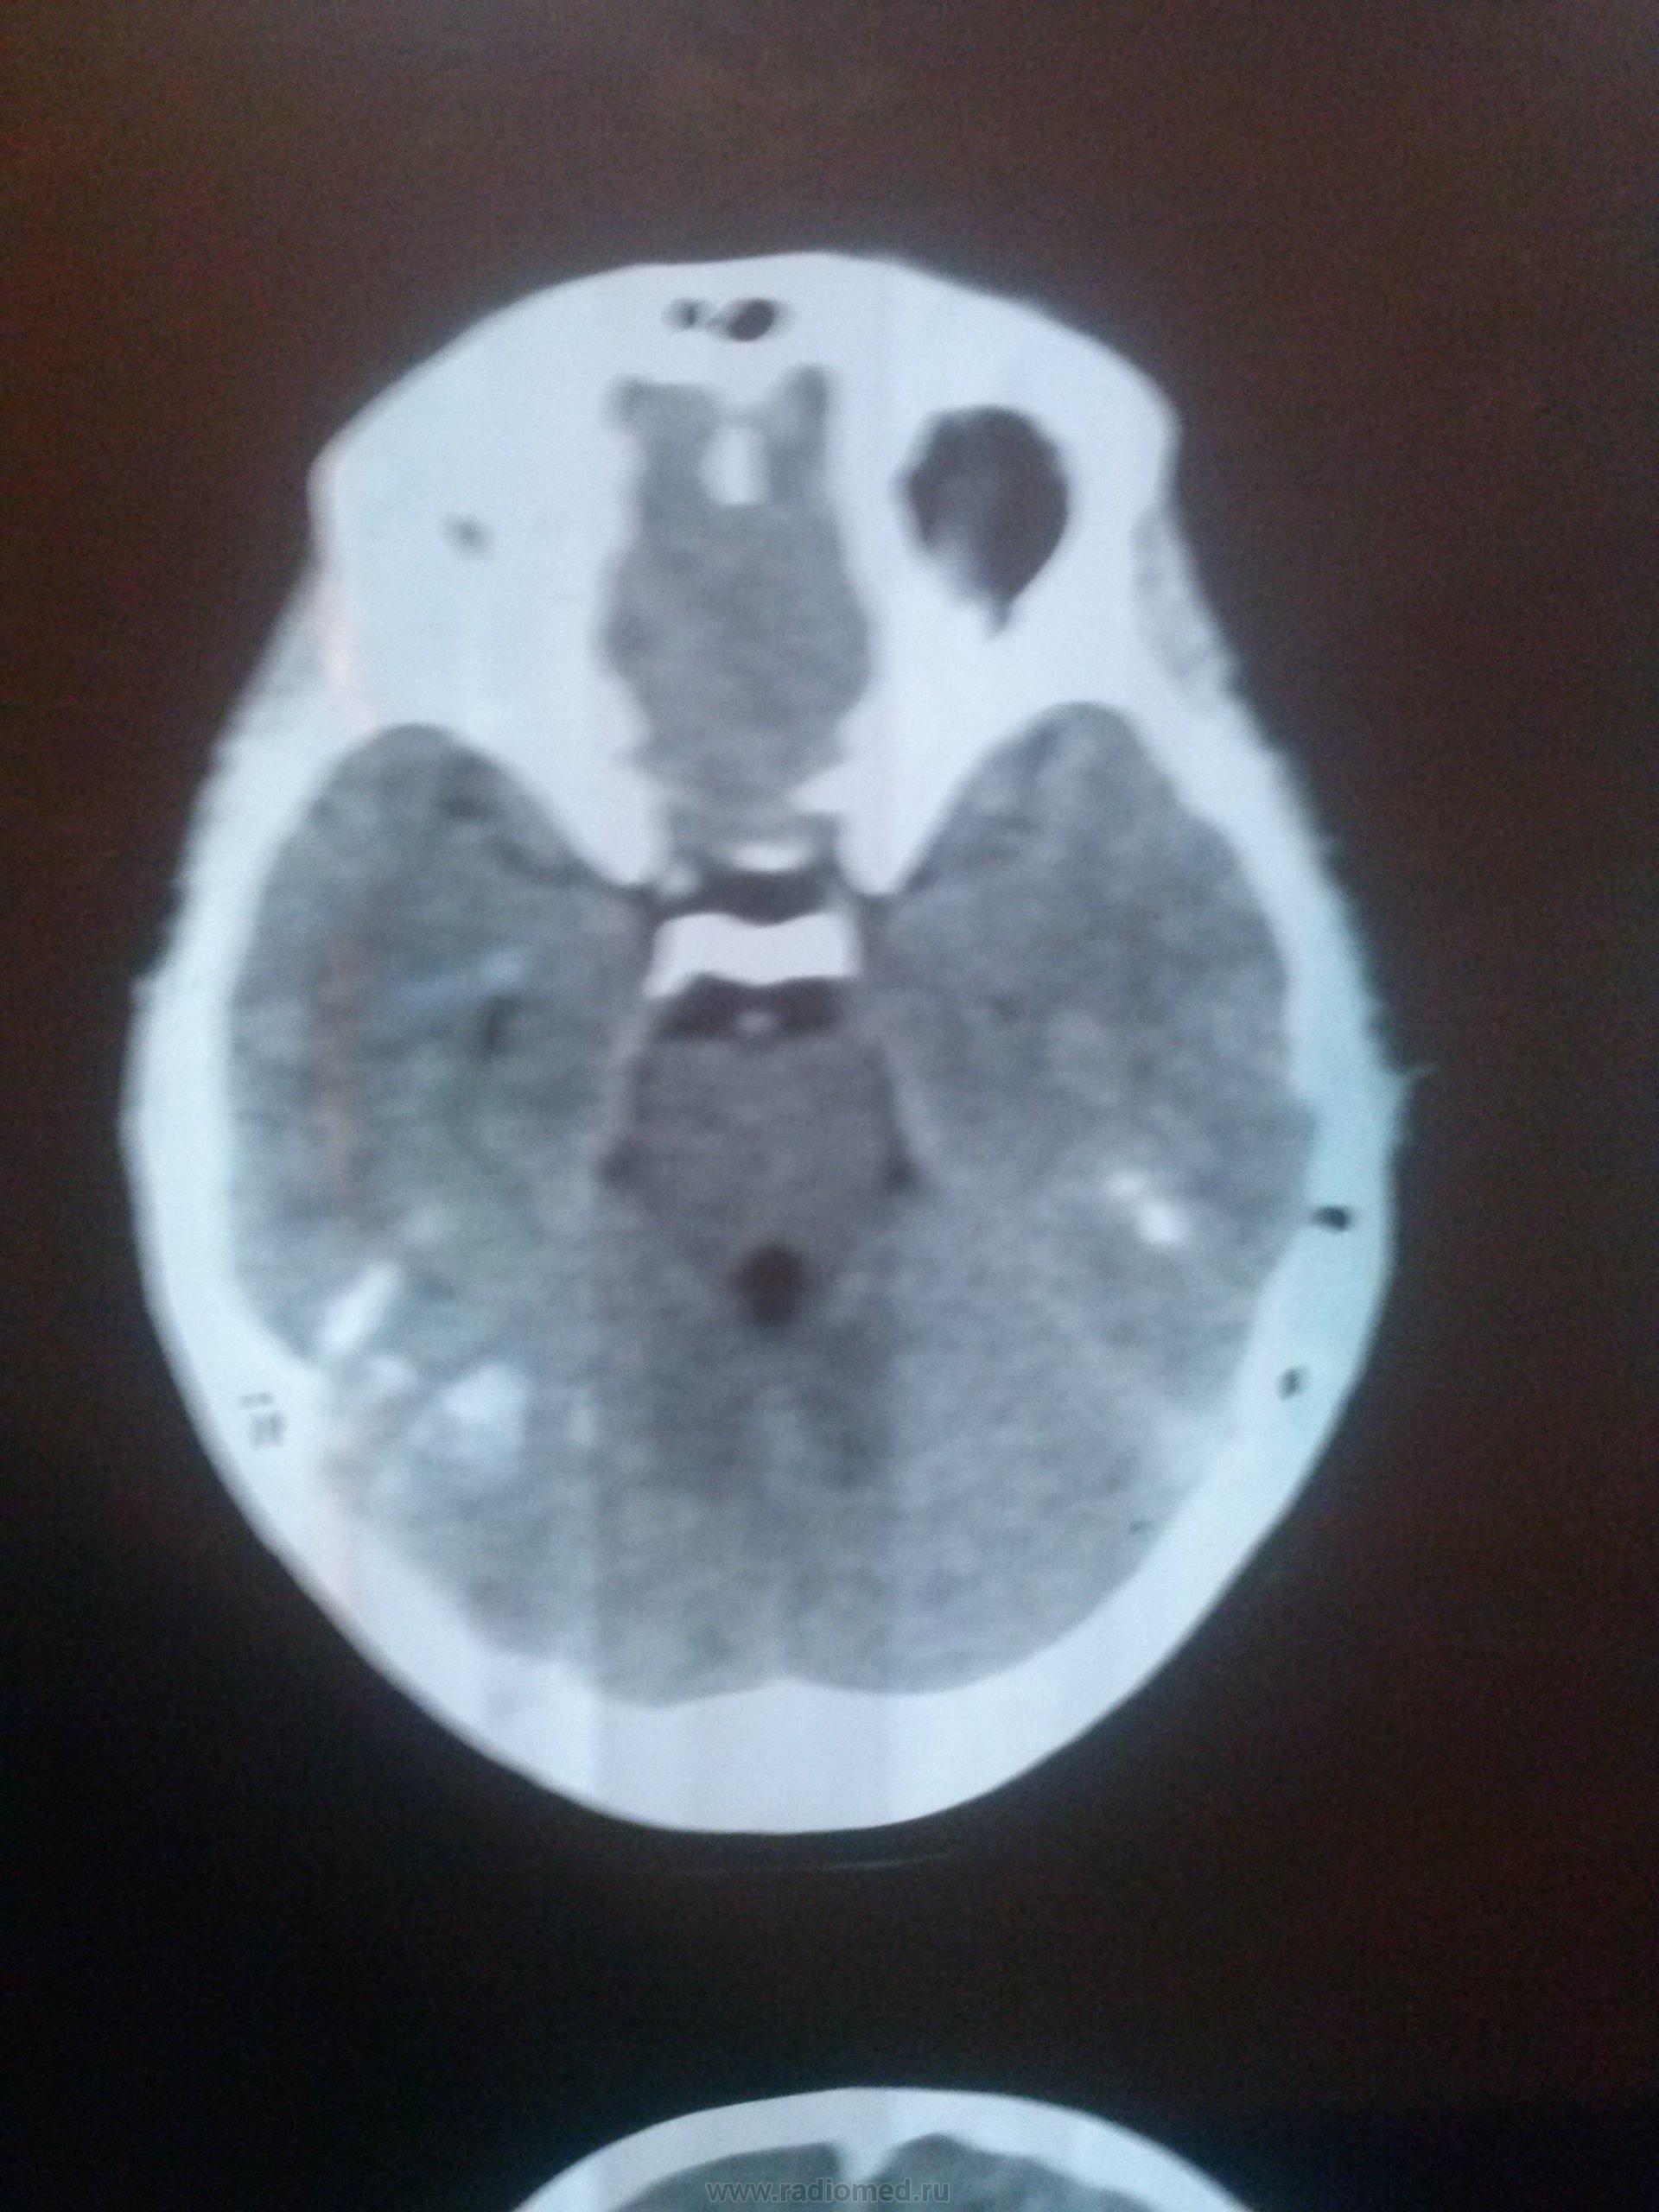

Вероятно, неровно голова лежала во время исследования и слева становятся заметны структуры орбиты, что за гиперденсивные участки в височных долях и правой гемисфере мозжечка? Так "порезались" костные структуры? Сложно судить по одному аксиальному срезу, еще и хотя бы в jpg.

Ну хоть так, очаговых и диффузных изменений в веществе головного мозга не вижу, вероятно так " прошел" срез и так " порезалось".